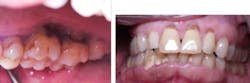

Case No. 3 — Mr. First Time

A 79-year-old African American male was diagnosed with chronic periodontitis. He had no prior dental care and presented with full dentition, no caries, and advanced bone loss with tooth mobility in molar areas. His chief complaint was a loose upper right tooth. The LANAP protocol was performed over two appointments with local anesthetic. Treatment was done in August 2012.

Mr. First Time before the LANAP protocol.

Mr. First Time is very pleased with his care despite his initial trepidation. Tooth mobility has lessened, and sensitivity is minimal despite the significant amount of calculus removal that was done and the resulting root exposure. The tooth with +3 mobility was removed. The patient realizes other teeth may need extraction, but at this time no additional extractions are planned. (November 2012)

Mr. First Time after treatment.